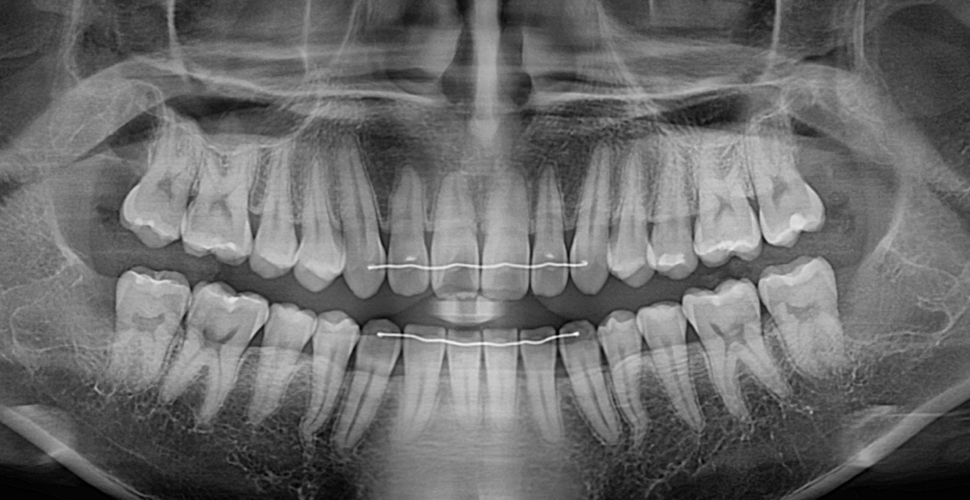

발치 전

사랑니 발치 후

20대 남성 환자분으로, 매복된 사랑니의 머리 부위와 뿌리부위 모두가 신경에 매우 근접하여 신경손상의 위험이 큰 상태였습니다.

어려운 케이스인 만큼 더 신중하게 발치를 진행하다 보니일반적인 경우보다 시간이 더 소요되었지만, 환자분께서 씩씩하게 잘 참으셔서 신경 손상 없이 안전하게 발치를 하였습니다.